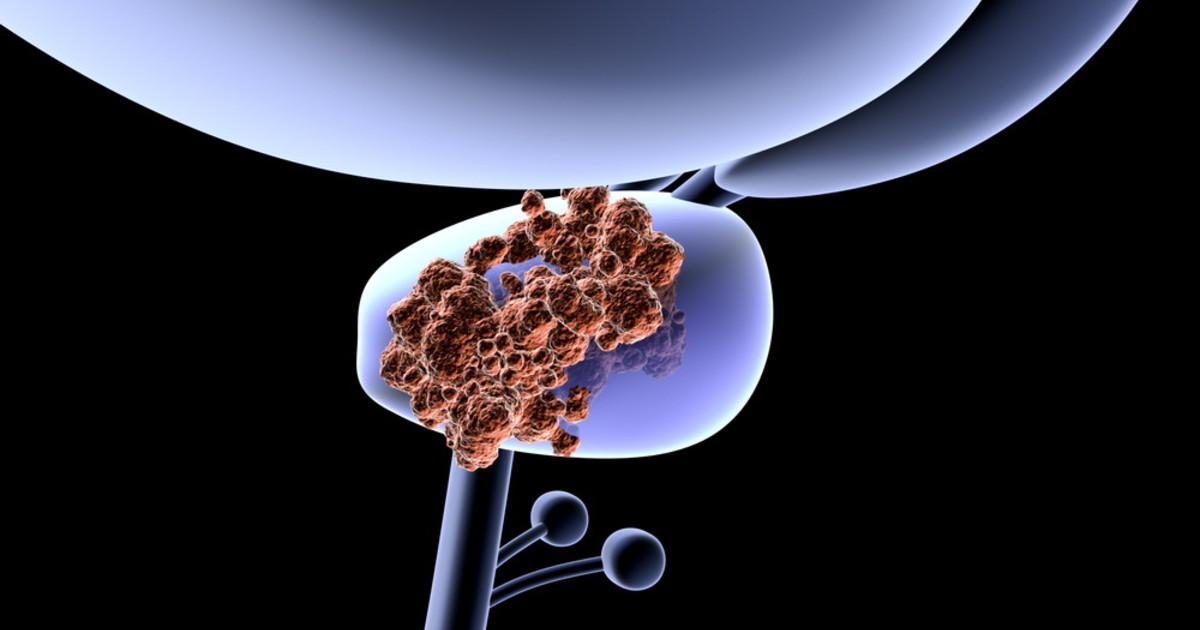

Tumore alla prostata, il meccanismo molecolare che ti condanna: lo studio, una scoperta decisiva?

Lo studio